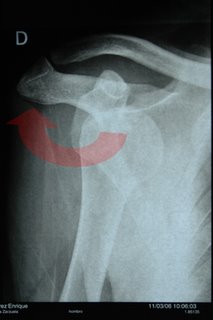

(Para Álvaro S., que preguntaba como escanear una radiografía… no lo sé, aunque sé que se puede. Para hacer ésta, he optado por la MacGyver way: simplemente he cogido la mía, la he pegado con cinta adhesiva sobre un papel en blanco y sobre el cristal de la ventana, y le he sacado una foto con la Nikon. Eso sí, encuadrar y disparar una Nikon D70 sólo con la mano izquierda tiene su aquel… :-)

Es una radiografía típica de luxación anterior el único problema es que la flecha etá al reves, para colocarlo hay que rotar hacia dentro y no hacia fuera, está más cerca de su sitio de lo que parece.

Enrique te convendría aprender como se coloca por si te pasa otra vez más lejos de un hospital, en cuanto se coloca deja de doler (siempre es mejor alguien experto pero si te pasa en medio del monte y tienes que esperar horas a una ambulancia (de todas forma haz caso a tu traumatólogo y no a mi).

Vaya caída que tuviste Enrique, cuando leía tu entrada sobre lo que te había pasado no creí que fuera tan grave como ahora que veo la radiografía…